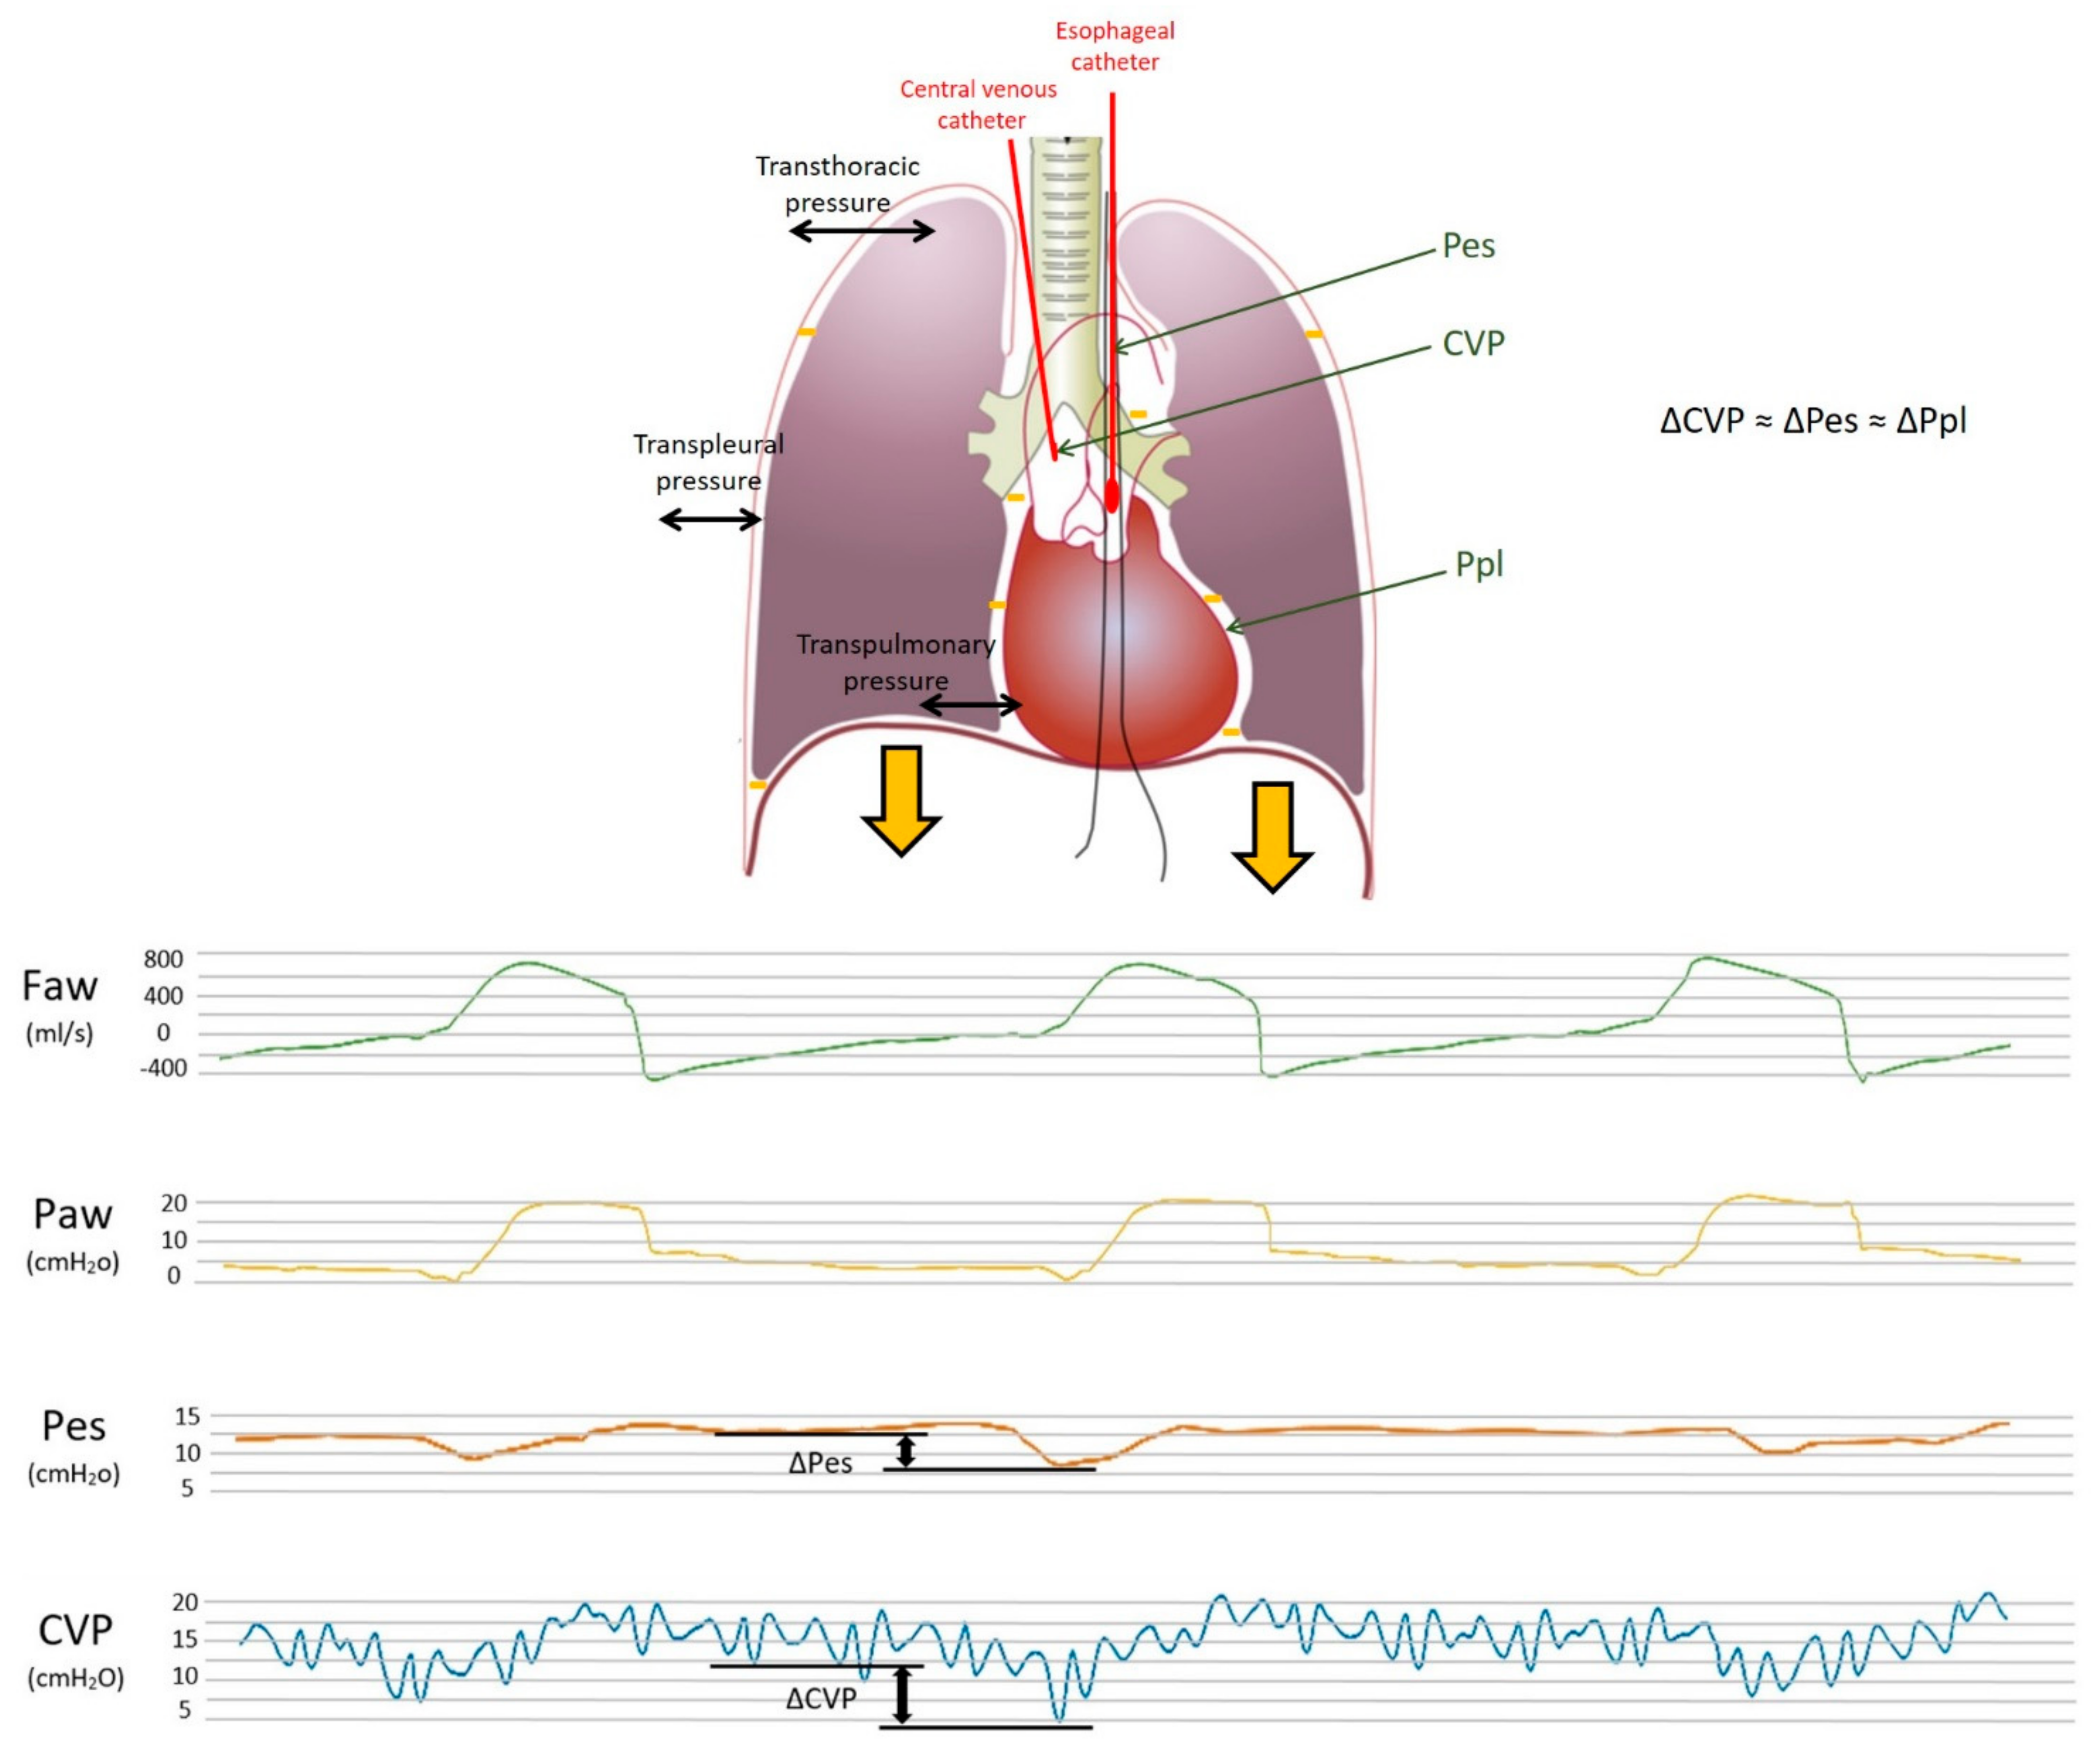

In particular, positive pressure mechanical inspiration increases intrathoracic pressure, thus causing a positive ΔCVP that reduces venous return. Conversely, spontaneous inspiration decreases intrathoracic pressure, thus causing a negative ΔCVP that increases venous return [30]. Indeed, this increase in venous return is limited; when the pressure drops below atmospheric pressure, the great veins collapse and develop a flow limitation. Therefore, based on these physiological assumptions, CVP appears to have respiratory oscillations that reflect intrathoracic (i.e., pleural) pressure changes. The extent of the respiratory swing in CVP was shown to be of a similar extent to that of Pes, which is also justified by the close anatomical position of the two measurement systems (as depicted in Figure 1 and Figure 2, upper panel).

In summary, CVP may represent a valid estimate of Ppl, similar to Pes, with the undeniable advantage of an almost ubiquitous presence of a central venous catheter in the critical care setting. This can provide an easy and rapid tool to evaluate partitioned respiratory mechanics and patient contribution during assisted breathing and guide titration of ventilatory support. The lower panel of Figure 2 shows the simultaneous recordings of flow, airway, esophageal and central venous pressures in a critically ill patient undergoing assisted mechanical ventilation. The use of ΔCVP as a surrogate of ΔPpl has been examined for decades, although it never became popular in the care of critically ill patients. In the following paragraphs, we summarize the findings of previous and recent papers that addressed this topic; the studies are divided into those reporting positive findings (i.e., CVP was found to be a reliable estimate of Pes or Ppl) and those reporting negative findings. Table 1 summarizes the factors influencing the relationship between CVP and pleural pressure; Table 2 reports the setting, methods and main findings of the studies included in the present review, and Table 3 summarizes the main biases and the limits of agreement of the different studies.

Figure 2. Upper panel: Model of the respiratory system and transmission of pleural pressure during inspiration. The respiratory system is composed of the lungs and the chest wall in series. The figure shows the different pressures within the system and the relative distending forces (in black). The difference between the alveolar and atmospheric pressure, i.e., the transthoracic pressure, is the pressure that distends both the lungs and the chest wall; the transpleural pressure (i.e., pleural minus atmospheric) is the pressure needed to distend the chest wall, whereas the transpulmonary pressure (i.e., airway minus pleural) is the pressure that distends the lungs. The thick, orange arrows depict the downward displacement of the diaphragm during inspiration, which lowers the pleural pressure (orange minus signs). This negative pleural pressure swing (ΔPpl) diffuses into the intrathoracic space and is transmitted through the esophagus to the balloon-tipped esophageal catheter (ΔPes) and through the superior vena cava to the central venous catheter (ΔCVP). Pes, esophageal pressure; Ppl, pleural pressure; CVP, central venous pressure. Lower panel: Pressure waveforms for CVP, Pes and Paw. Central venous pressure swings (CVP, blue wave), esophageal pressure swings (Pes, orange wave), airway pressure swings (Paw, yellow wave) and flow (Faw, green wave) during assisted mechanical ventilation.